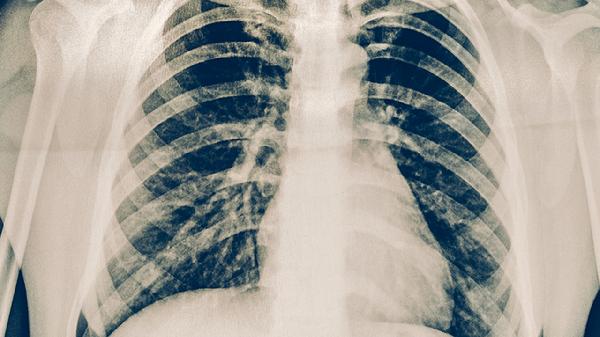

原發(fā)性肺結核典型表現為原發(fā)綜合征三聯征,包括肺內原發(fā)病灶、淋巴管炎和肺門淋巴結腫大。肺結核的病理表現更為多樣,繼發(fā)性肺結核常見浸潤性病變、空洞形成或纖維鈣化灶。

原發(fā)性肺結核在X線胸片上多顯示為啞鈴狀陰影,即原發(fā)灶-淋巴管炎-淋巴結炎的典型組合。肺結核的影像學表現因類型而異,繼發(fā)性肺結核常見上葉尖后段或下葉背段的斑片狀、云霧狀陰影。